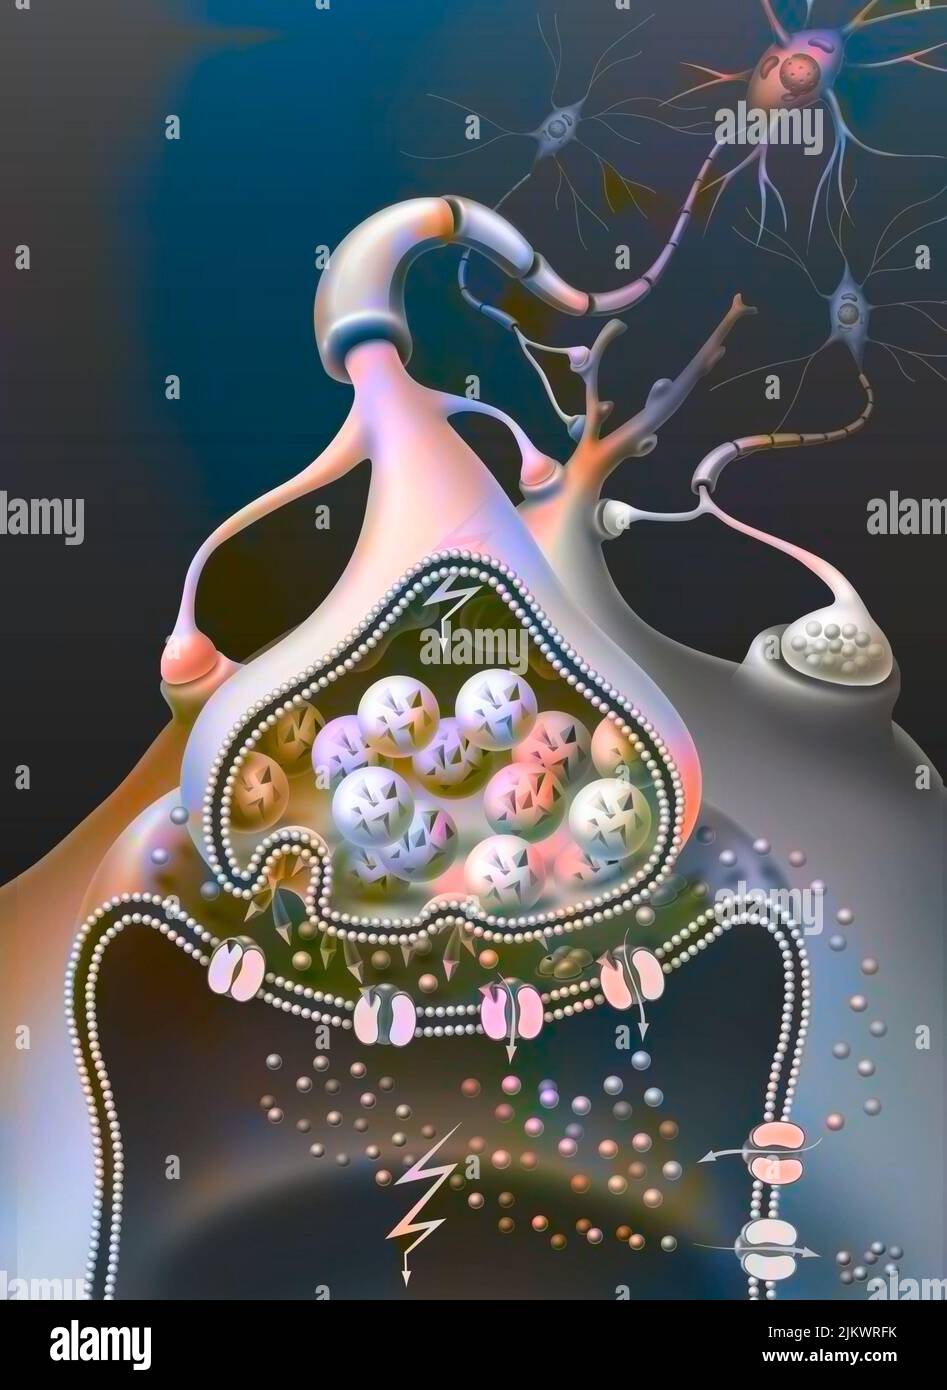

RF2JKWRF2–Pla (potentialisation à long terme) après une semaine, étape 2 : la synapse est stimulée avec une plus grande efficacité.

RF2JKWR03–Action des sels minéraux et des vitamines sur la transmission des impulsions nerveuses aux synapses.